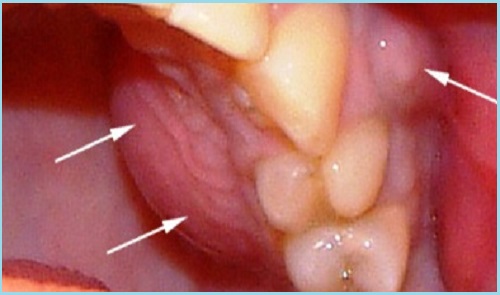

Последствия

При отсутствии лечения острый периодонтит может привести к неприятным осложнениям — периоститу (флюсу), а затем к абсцессам и флегмонам челюстно-лицевой области. Возможно развитие острого остеомиелита или гайморита.

При прогрессировании хронического периодонтита чаще всего образуются кисты, способные в процессе роста охватывать корни соседних зубов. Также возможно прорастание кист в гайморову пазуху. Возможно нагноение кист с образованием хронического свища (как в полость рта, так и через кожу околочелюстной области).